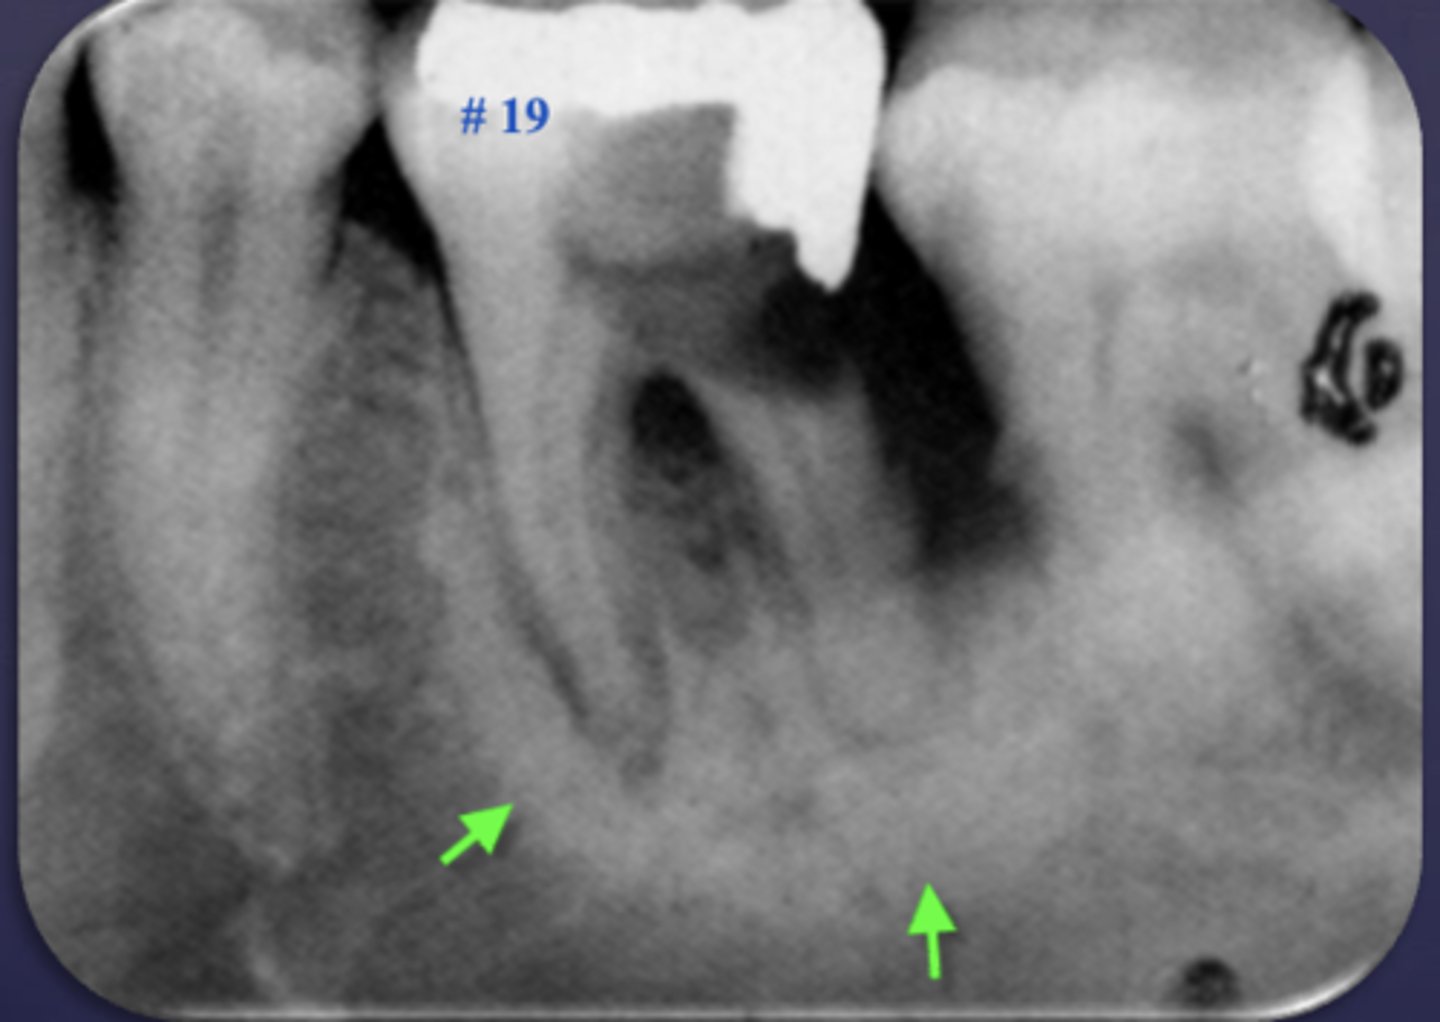

These arrows are pointing at what?

moth-eaten appearance of acute osteomyelitis

The moth eaten appearance is associated with what?

acute osteomyelitis, mixed radiolucent/radiopaque areas